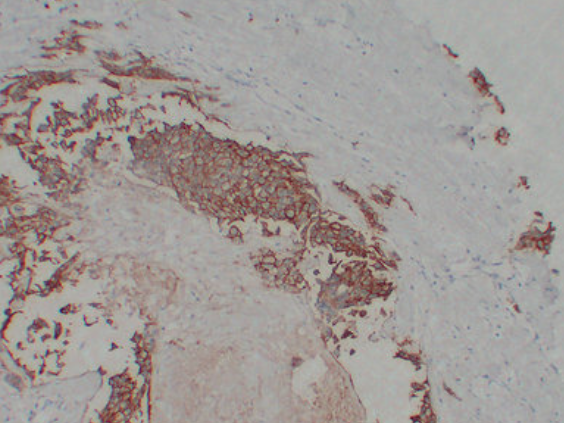

IHC (Immunohistochemistry)

(Immunohistochemistry analysis of paraffin-embedded Breast carcinoma using ErbB 2 antibody.High-pressure and temperature Sodium Citrate pH 6.0 was used for antigen retrieval.)